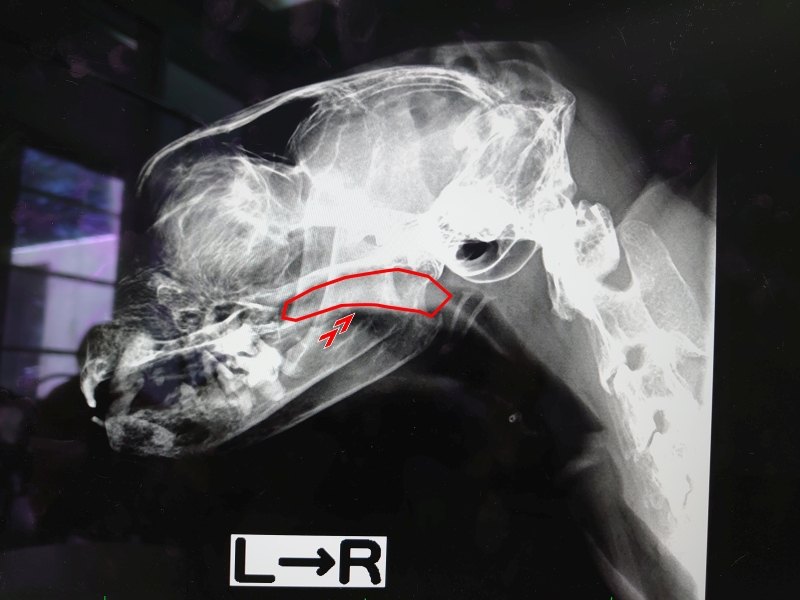

markのレントゲン写真

そかこんななってるんだ..なんて思いながら先生からのお話しを聞く

鼻咽頭内が少し狭窄しているように見えるけど、やはりレントゲンでは詳しくはわからない

CTと内視鏡でちゃんと見ないと判断できないとのこと

鼻が詰まっている原因としては、感染、炎症、異物、腫瘍、狭窄

これらのうち、鼻水が出ていないmarkの症状からすると異物か狭窄ではないかとのこと